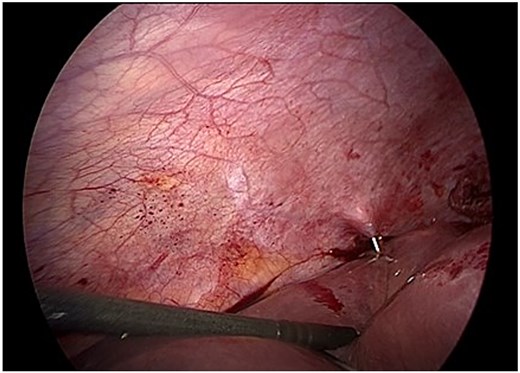

Given the size and location of the cyst, complete pericystectomy was not indicated due to proximity to major vascular structures and the absence of complications. Instead, careful evacuation of the membrane and limited resection of prominent pericystic tissue was performed, preserving liver integrity (Fig. 4). A drain was left in place due to the potential for undetected biliary communication.

Careful evacuation of cystic material and limited resection of prominent pericystic tissue. Complete pericystectomy was not indicated due to cyst size and location.